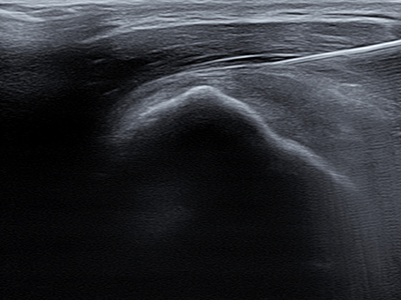

Rotator Cuff Tear

회전근개 파열이란?

회전근개 파열은 ‘회전근개’라고 불리는 어깨관절을 둘러싸고 있는

4개의 힘줄(극상근, 극하근, 소원근, 견갑하근) 중

하나 이상이 파열되는 질환

입니다.

회전근개는 어깨의 안정성을 유지하고, 팔을 들어올리고

회전시키는 동작을 가능하게 하는 중요한 역할을 담당합니다.

어깨 힘줄은 한번 파열되면 자연치유가 어려워

조기 발견과 치료가 중요합니다